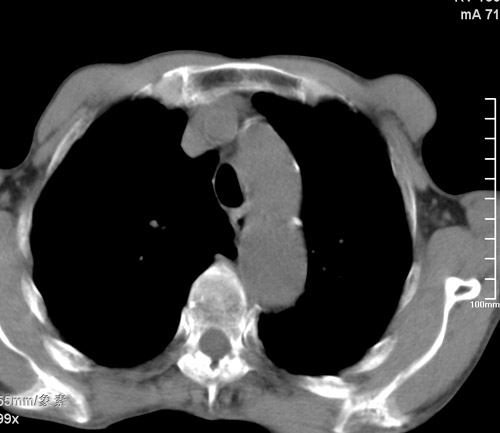

标题: CT17529:男 76 胸背部不适半月 胸透支气管炎 行CT检查 [打印本页]

标题: CT17529:男 76 胸背部不适半月 胸透支气管炎 行CT检查

意见 老年肺 少许炎症 肺大泡 右肺门略大 但支气管通畅  请各位高手指教如何下意见

支持楼主意见,右肺门略大,可能为肺动脉增粗.

慢支肺气肿,肺动脉高压.